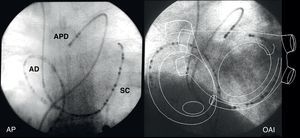

Figura 15. Imágenes fluoroscópicas de catéteres-electrodo multipolares en la aurícula derecha, seno coronario y arteria pulmonar derecha en proyecciones anteroposterior y oblicua anterior izquierda. El esquema de la anatomía auricular muestra las áreas que registran estos catéteres. AD: aurícula derecha; AP: anteroposterior; APD: arteria pulmonar derecha; OAI: oblicua anterior izquierda; SC: seno coronario.